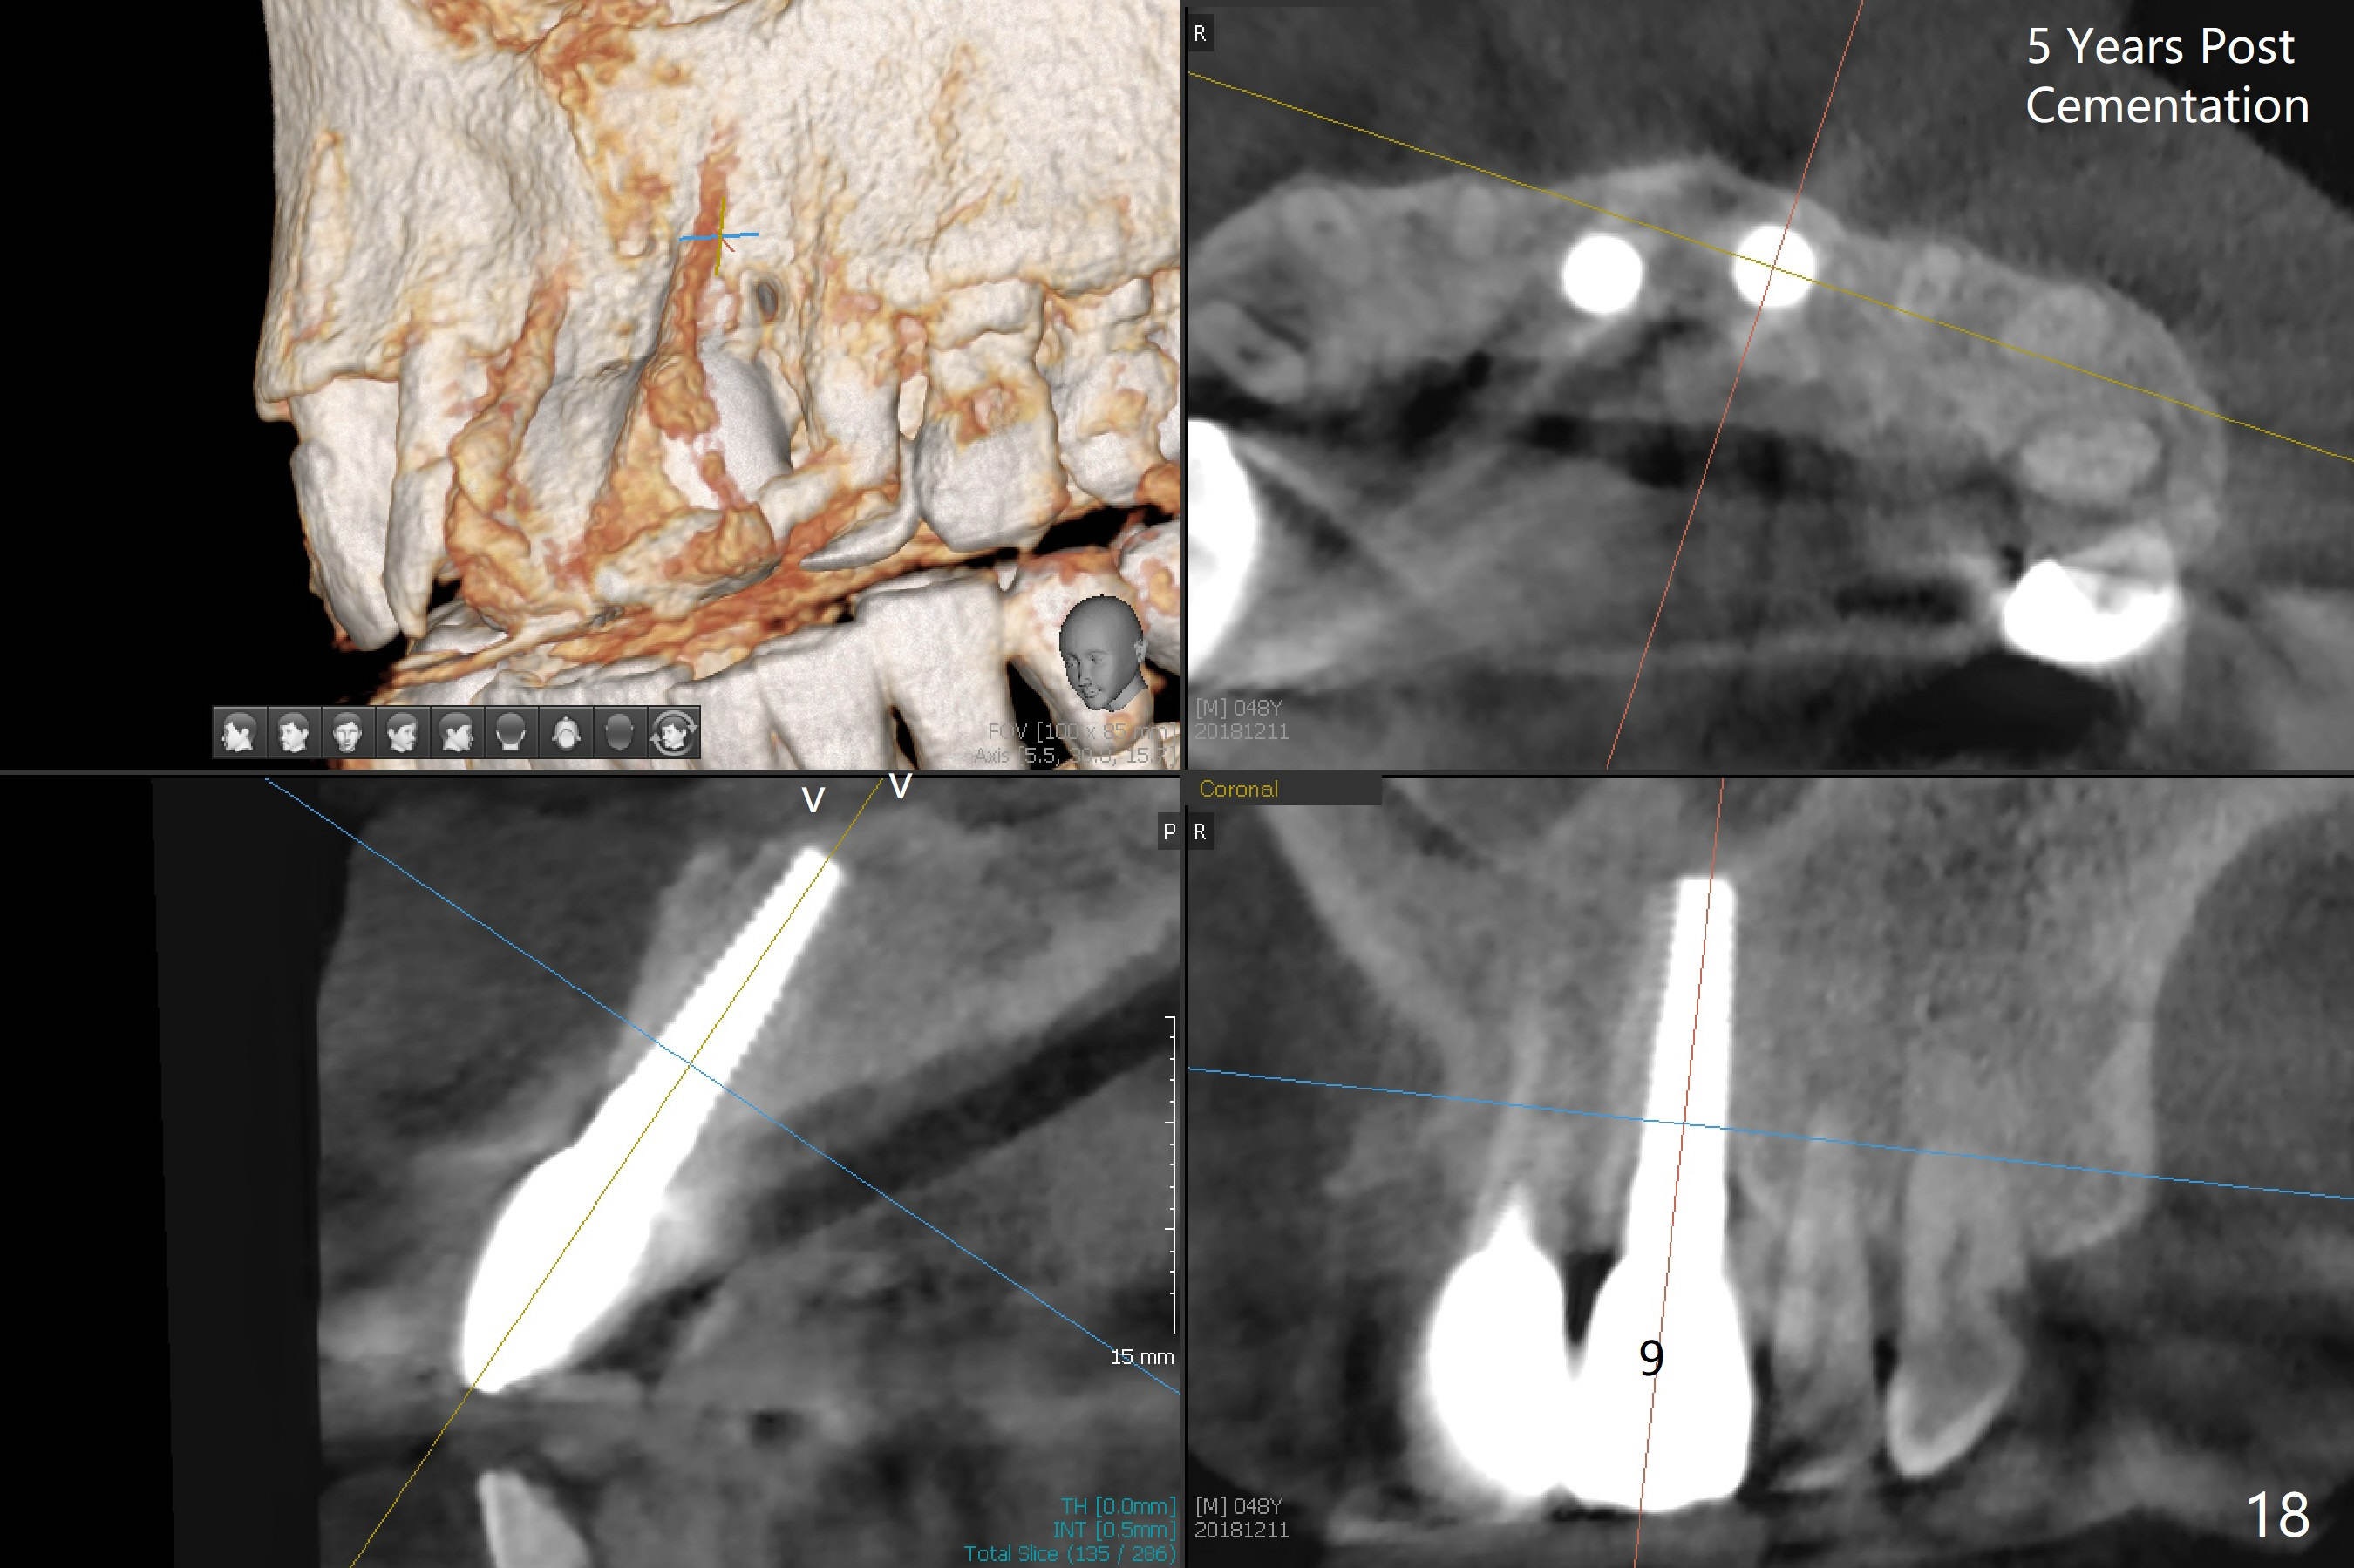

Nasal Lift Associated with Incisor Immediate Implants

A 44-year-old man has advanced periodontitis (Fig.1,2). The infection resolves substantially 5 days post scaling & root planing (Fig.4,5). The two centrals have severe bone loss (Fig.3) and are going to be replaced by 5x20 mm implants (Fig.6).

Definitive restoratons (Zirconium crowns) are seated (Fig.15,16). There is no sign of infection. The patient is pleased. In fact the nasal floor does not seem to have been lifted by the implants, as revealed by CT taken 5 years post cementation (Fig.17,18).